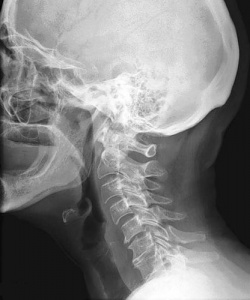

Шейный отдел располагается в верхней части позвоночного столба и состоит из позвонков. Он имеет легкий изгиб в виде буквы “С”, при этом выпуклая сторона обращена вперед. Это физиологическое состояние.

При исследовании шейной области врач может сделать 2 снимка в двух проекциях: боковой и передней.

В норме позвоночник человека незначительно выгнут вперед. Благодаря рентгенографии можно выявить остеохондроз первой или второй стадии, переломы, вывихи.

- При остеохондрозе первой степени на рентгенограмме высота межпозвонковой щели снижается на расстоянии, не превышающем 1/3 тела позвонка, а при второй степени патологии данный сегмент уменьшается до половины тела позвонка.